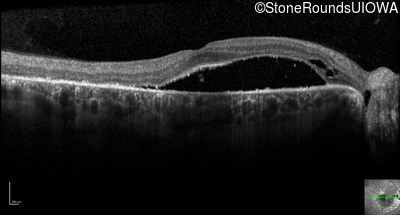

Optical Coherence Tomography - Right - 20/32 +2

Exemplar / OCT Stack